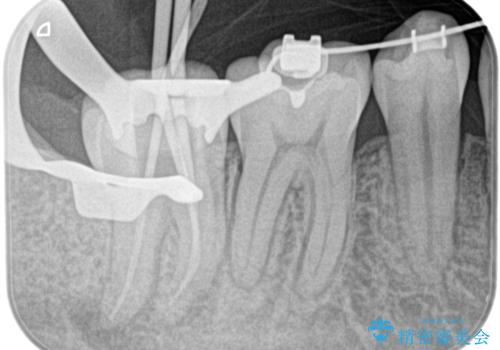

- 奥の歯茎にニキビみたいなものができたことを主訴に来院されました。

来院時は特に痛みはありませんでしたが、5年ほど前は痛みがあり、他院で虫歯の治療をしたことがあるとのことでした。

歯髄検査をし、歯髄壊死と診断できたため治療を介入しています。

咬合面の修復材料を除去すると内部に細菌の塊である多量のカリエスが残存しており、それが原因で歯髄が壊死したと考えられます。

治療中、細菌の除去を徹底的に行えるように顕微鏡とラバーダム(ゴムのシート)を用いて行いました。